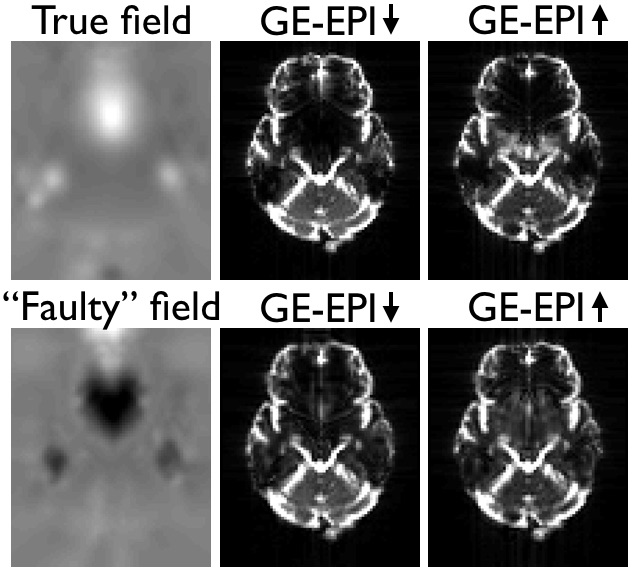

|

| Pairs of SE- and GE-EPI images acquired with opposing phase-encode directions. Note how the distortions are the same as evidenced by the similar shape. But that in the GE-EPI images there are also signal dropout that differ between the two image. |

This means that the model underlying topup is not valid for these data, and the consequence will be that topup will attempt to "explain" the observed differnces due to signal modulation as being caused by distortions. It can do a surprisingly good job at that, producing two "corrected" images that look very similar. But that is potentially at the cost of an estimated field that is far from the true field, and "corrected" images that are potentially even worse distorted than to start with. Below is a comparison between a field estimated from a pair of Spin-Echo(SE)-EPI images and from a pair of GE-EPI images. The images have been simulated using the physics based MR-simulator POSSUM, so the truth is known. As can be seen the field estimated from the GE-EPI pair is almost the negation of the true field. This means of course that the "corrected" images are worse than the original images.

![]() |

| Both panels show the two original (distorted) images on the left, the field estimated (by topup) to minimise the difference between the corrected images in the middle and the two corrected images on the right. The left panel shows SE-EPI images (e.g. diffusion b0-images) and the right panel shows GE-EPI images (e.g. fMRI images). Note that topup appears to have done a good job of correcting for distortions in both cases, but that the estimated field for the GE-EPI data is almost the negation of the true field. | |